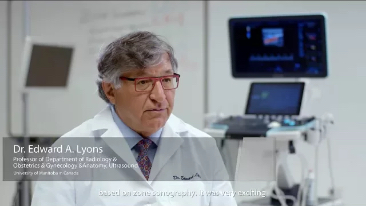

Resona 7

New Waves in Ultrasound Innovation

With Zone Intelligence

Since the company was founded, Mindray has been continuously exploring new ways to improve diagnostic confidence. Powered by the most revolutionary ZONE Sonography? Technology, Resona 7ŌĆÖs new ZST+ platform brings ultrasound image quality to a higher level by zone acquisition and channel data processing.

As well as the premium level image quality, Resona 7 also enhances clinical research capabilities with the revolutionary V Flow for vascular hemodynamic evaluation, and the most intelligent plane acquisition from 3D datasets for fetal CNS diagnosis. Combining the most intuitive gesture-based multi-touch operation and all the essential clinical features, Resona 7 is truly leading new waves in ultrasound innovation.